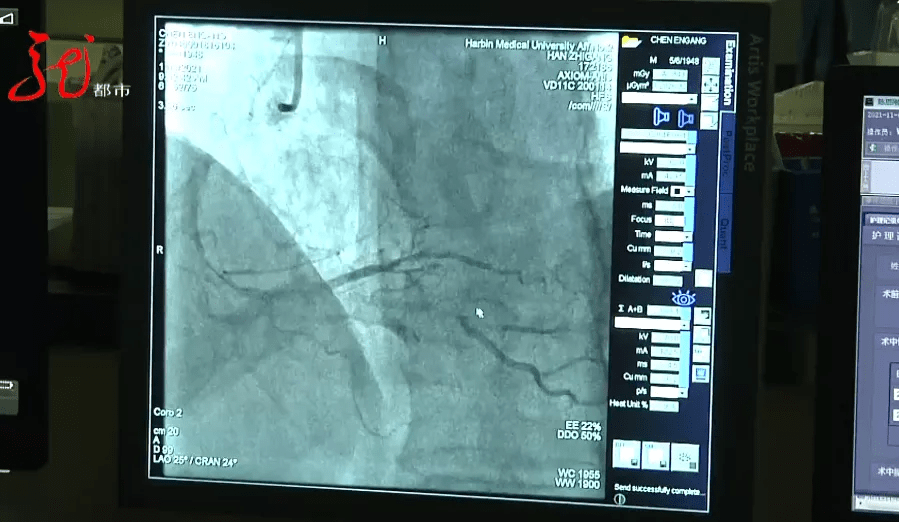

这处病变在我们判断 , 接近90%的狭窄 , 如果不及时治疗 , 它会引起病人的不适 , 引起心脏缺血 , 引起心绞痛 , 那么这时候就会导致心肌梗死 。

这名患者心脏后降支血管堵塞90% , 也就是心梗 。 哈医大二院心内科韩志刚医生分析 , 如果任由病灶发展 , 后果将无法估量 。

哈医大二院心内科主任医师 副教授 韩志刚

中等大小的血管如果突然闭掉的话 , 那么很有可能导致的就不光是心肌梗死 , 可能导致他会突然心跳骤停 , 如果抢救不及时 , 就会引起心源性猝死 。